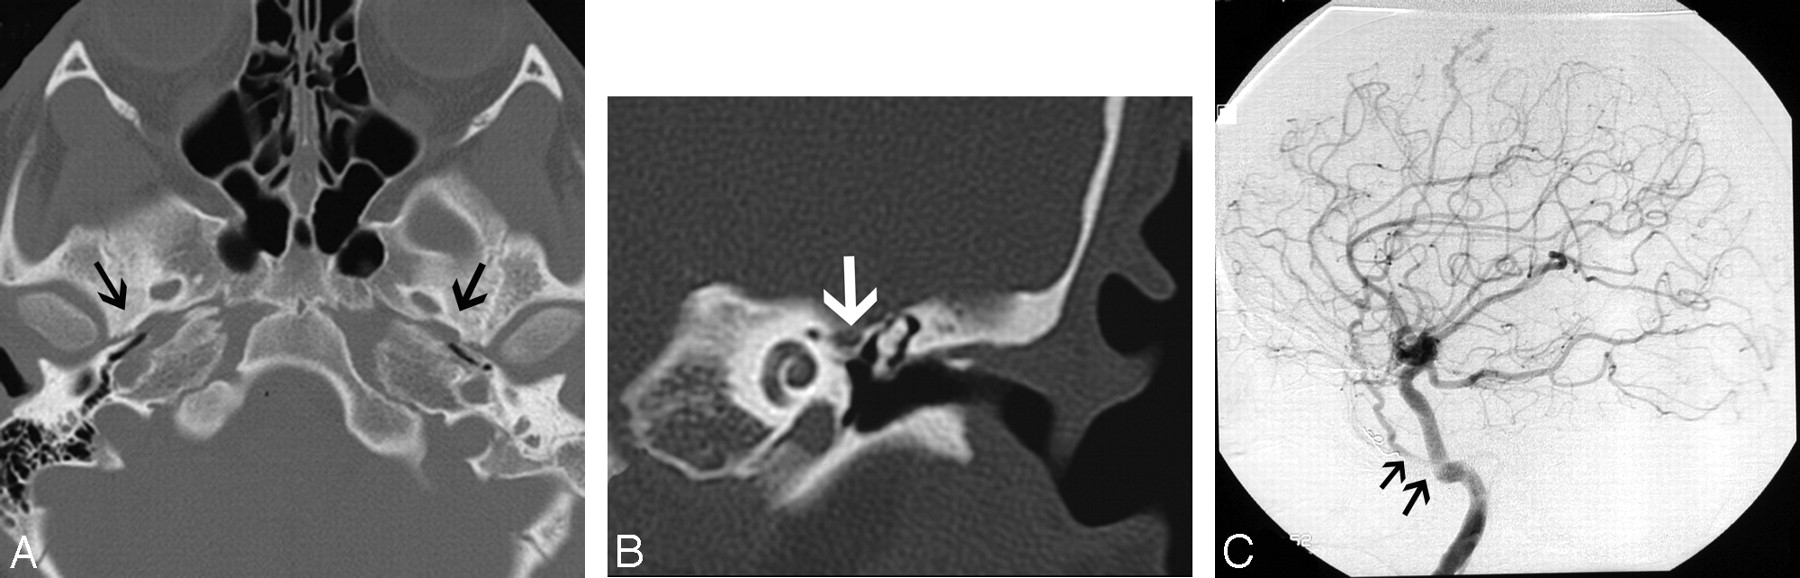

Absence of the foramen spinosum and enlargement of the proximal tympanic facial nerve canal may indicate the presence of a PSA (Fig 8A–C). The stapedial artery is normally present in the fetus but undergoes regression before birth. It arises from a normal or aberrant ICA (approximately 30% of all aberrant ICAs are associated with a PSA). The PSA typically runs through the obturator foramen (the space between the crura of the stapes) and across the promontory in the middle ear, where it can sometimes be identified. The PSA then runs along the tympanic portion of the facial nerve canal near the geniculate fossa, finally exiting the facial nerve canal to enter the middle cranial fossa to become the middle meningeal artery.

A 30-year-old man with PSA. A, Axial CT image demonstrates absence of the foramen spinosum bilaterally (black arrows). B, Coronal CT image in the same patient shows enlargement of the tympanic part of the facial nerve canal, another indirect imaging sign of PSA. C, Lateral DSA image of the internal carotid injection shows the PSA arising from the ICA (arrows).

When the stapedial artery persists beyond the fetal period, the middle meningeal artery does not develop from the internal maxillary artery and the foramen spinosum remains undeveloped. The absence of the foramen spinosum is an important CT finding that should alert the radiologist to a possible PSA (Fig 8A). However, these findings do need to be interpreted cautiously because the foramen spinosum may be absent in ≤3% of all skull base CT studies.35 The presence of additional signs such as a subtle enlargement of the tympanic segment of the ipsilateral facial nerve canal on coronal CT images, just inferior to the lateral semicircular canal, may raise the index of suspicion (Fig 8B), and DSA can be used for confirmation (Fig 8C). Most patients with a PSA remain asymptomatic and only rarely present with pulsatile tinnitus. The physical examination in some patients may show a red retrotympanic mass, which may provide useful clinical correlation for the imaging findings.